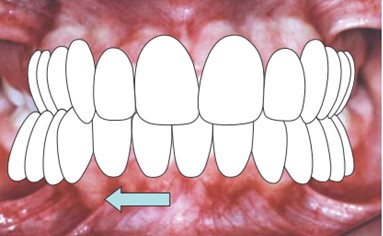

A mordida cruzada ocorre quando os dentes superiores e inferiores não se alinham corretamente ao fechar a boca.

Em uma mordida normal, os dentes superiores devem se posicionar ligeiramente à frente dos inferiores. No entanto, na cruzada, os dentes inferiores podem se sobrepor aos superiores em algumas áreas, causando um desalinhamento que pode ser tanto estético quanto funcional.

Esse desalinhamento pode afetar apenas um dente, um grupo de dentes ou a arcada dentária inteira, e pode ocorrer tanto na parte anterior quanto posterior da boca.

Além disso, a mordida cruzada pode ser uni ou bilateral, afetando apenas um lado ou ambos os lados da arcada dentária.

A mordida cruzada anterior ocorre quando os dentes anteriores inferiores se posicionam à frente dos dentes anteriores superiores.

Esse tipo de mordida é facilmente identificável, pois altera a estética do sorriso de forma significativa, além da possibilidade de causar desgastes nos dentes, problemas de fala e dificuldade na mastigação.

Em alguns casos, essa condição pode ser confundida com uma má oclusão de Classe III, que também é caracterizada pela protrusão da mandíbula.

A mordida cruzada posterior ocorre quando os dentes posteriores inferiores se sobrepõem aos superiores.

Este tipo de mordida pode afetar um lado ou ambos os lados da boca.